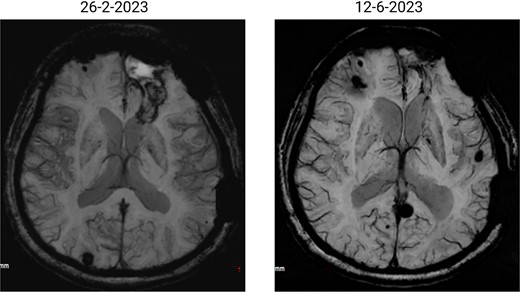

The patient has undergone multiple rounds of MRI and CT (Fig. 3) imaging examinations, the results of which have consistently shown a morphology suggestive of recurrent ICH. T2-weighted (Fig. 4) and susceptibility-weighted (SW) MRI (Fig. 5) showed many cerebral cavernous malformations (CCMs) scattered across both cerebral hemispheres, mainly located in the left parietal, frontal, and occipital lobes, with some lesions extending into the brainstem. Multiple lesions presented with a mixed signal intensity corresponding to different stages of haemorrhage and blood degradation products. There was noticeable hemosiderin deposition, indicating the presence of chronic microhaemorrhages. These deposits were particularly extensive in the left parietal lobe, corresponding to the site of the largest and most symptomatic haemorrhage. Regions of gliosis were observed near the haemorrhagic lesions, indicating long-term damage from previous haemorrhages. SWI confirmed the presence of multiple microhaemorrhagic lesions in the parenchyma and subcortical white matter, complicating the clinical picture.

Brain MRI showing dynamic haemorrhage. (a) T2-weighted MR image showing multiple CCMs. The highlighted portions indicate areas of hemosiderin deposition associated with previous haemorrhages. (b) post-contrast T1-weighted MR images showing the enhancement patterns of CCMs and the extent of the surrounding oedema.